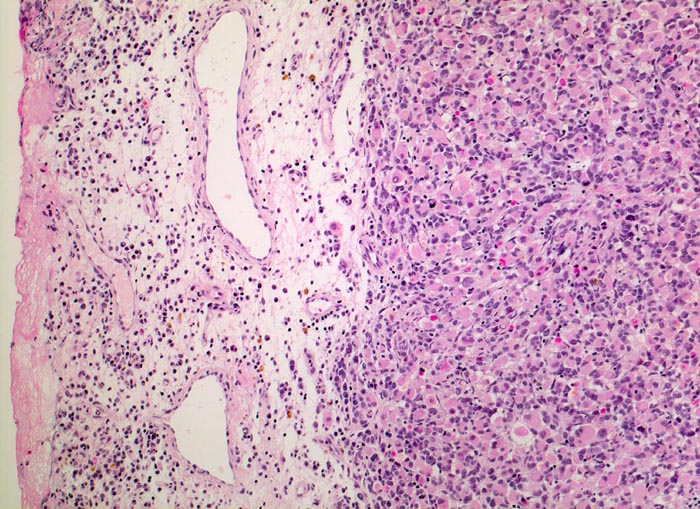

embryonales Rhabdomyosarkom

Links im Bild ödematöses Bindegewebe mit gemischtem Entzündungsinfiltrat und Blutungsresiduen (braune Hämosiderinablagerungen). Der expansiv wachsende Tumor rechts im Bild hat keine Kapsel und besteht aus kleinen Gruppen primitiver Zellen mit rundlichen Kernen und praktisch fehlendem Zytoplasma sowie zahlreichen zytoplasmareichen Rhabdomyoblasten.

Schmerzloser rasch wachsender Tumor im oberen inneren Quadranten der Orbita mit Verdrängung des Bulbus nach temporal. Diplopie.